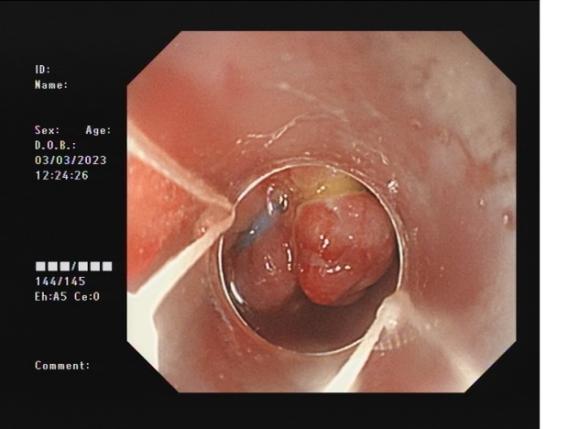

3b2d4fd666c540e5a8957f178dfb0b6b.Jpeg38cdda0ed1d245cfa077b1a308a229ca.Jpeg

內(nèi)痔                    內(nèi)鏡下內(nèi)痔硬化治療

內(nèi)鏡下內(nèi)痔硬化術(shù):治療I-Ⅲ度內(nèi)痔伴有內(nèi)痔相關(guān)癥狀;I~Ⅲ級(jí)內(nèi)痔飲食及藥物治療無(wú)效;內(nèi)痔手術(shù)后復(fù)發(fā),肛門反復(fù)手術(shù)后不能再次手術(shù);恐懼外科手術(shù),不愿意接受手術(shù)治療;高齡、高血壓、糖尿病和嚴(yán)重的系統(tǒng)性疾病,不能耐受外科手術(shù)等。